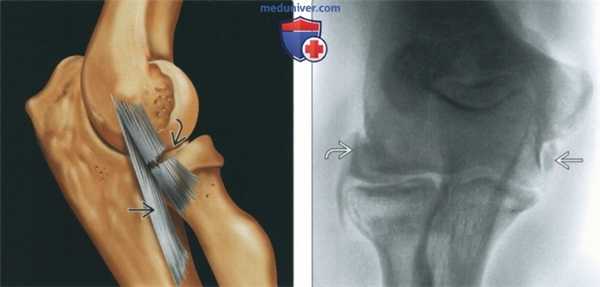

(Слева) МР-артрография в режиме PD FS, сагиттальный срез: визуализируются последствия коано-хрящевого повреждения - свободное тело в переднем отделе сустава, остеофит и синовит.

(Справа) МР-артрография в режиме Т1ВИ, коронарный срез: в головке мыщелка плечевой кости отмечается локальный глубокий дефект хряща. Прилежащий отдел хряща имеет неровный контур. Пациент молодого возраста занимался бейсболом.